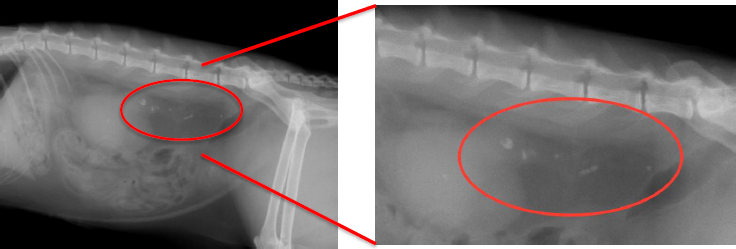

![]() |

|

レントゲン写真はお腹を横から撮ったものです。 尿管という腎臓と膀胱をつなぐ管に、多数の結石の白い影が見えました。 尿の通り道に多数の結石が詰まっている状態です。 結石が尿管につまり、先へ尿が流れなくなり腎臓に尿が溜まっている状態です。重度の腎機能の低下を認めました。 |